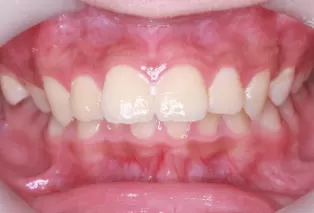

Intraoral photos